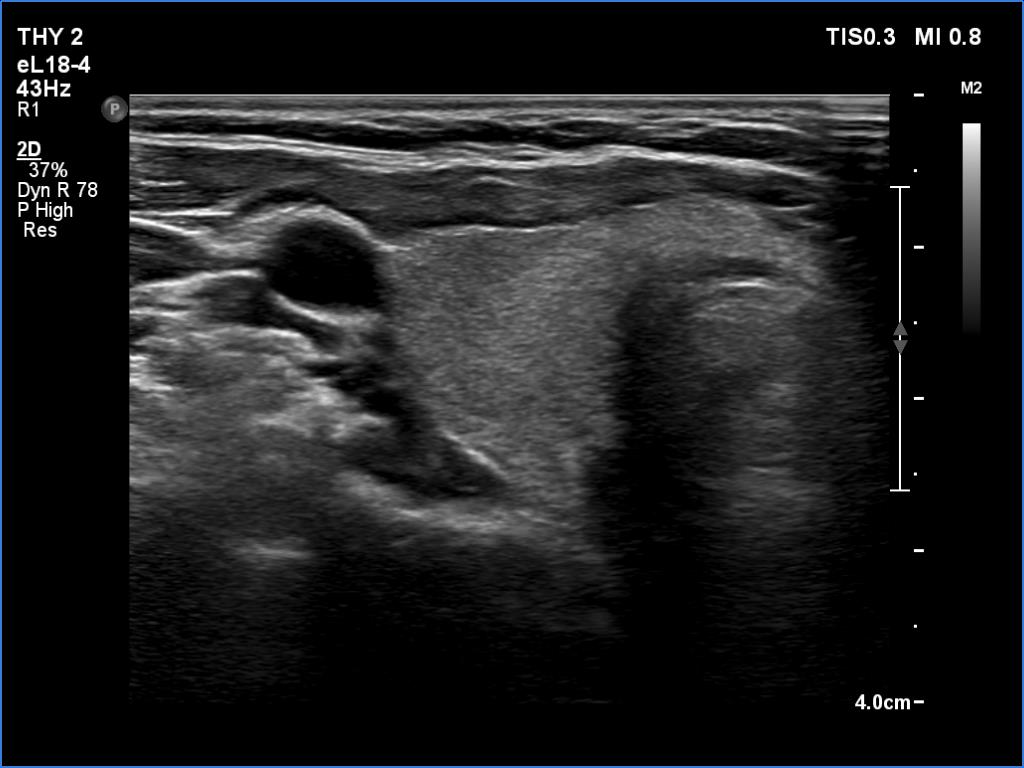

Initial examination (first row of images):

Clinical presentation: A 39-year-old woman was referred for evaluation of neck complaints lasting for more than a month. The patient had fever, neck pain. She has got two courses of antibiotics and non-steroid anti inflammatory drugs which had no effect.

Palpation: The right lobe was painful and hard while the left lobe was tender.

Laboratory examination: TSH 0.01 mIU/L, FT4 29.1 pM/L, FT3 7.45 pM/L, CRP 31.2 mg/L.

Ultrasonography: The thyroid presented with hypoechoic areas which had blurred borders. The echogenicity index was approximately 65% in the right and 20% in the left lobe. The thyroid was almost completely avascular.

Diagnosis: subacute, granulomatous de Quervain's thyroiditis.